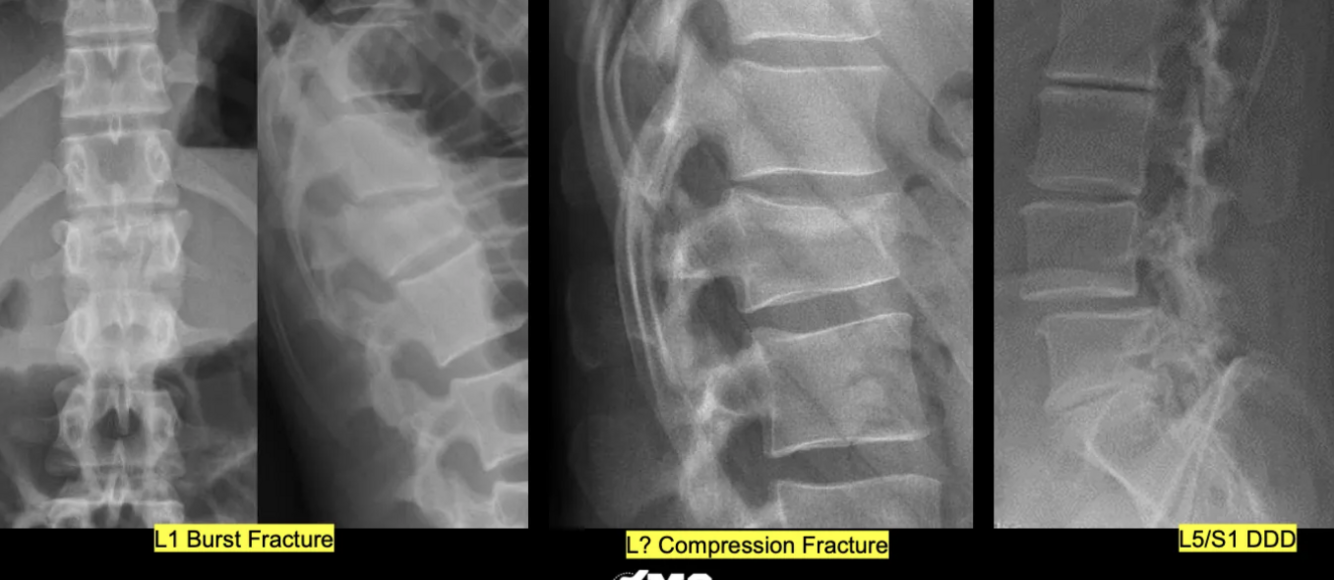

What are the pathologies in this picture?

What are the pathologies present in this picture?